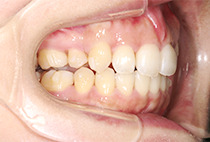

出っ歯と前歯のガタつきにお悩みだった20代女性の症例です。

前歯のガタガタ、中心のずれ、顎のずれ、外科矯正は避けたい

矯正は「歯並びを治す」だけではありません。

当院では、呼吸・噛み合わせ・顔貌バランス・美容までトータルに整える顎顔面治療を行っています。